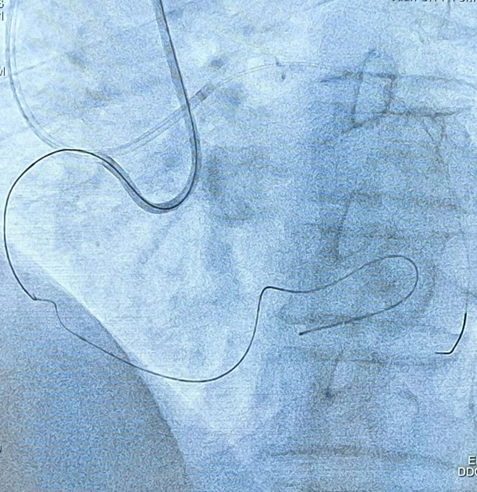

通过严重迂曲心外膜通道的逆向导丝有了逆向导丝指引,术者再次尝试正向进入靶病变,应用 CART 技术,通过手感对斑块软硬程度的认知,经过延长导管与微导管配合,正向反复尝试、升级导丝,最终使用导丝正向通过夹层通路。正向导丝与逆向导丝慢慢会师,双向导丝交汇,多体位证实导丝无限接近。继续操作正向导丝缓慢前行,顺利进入逆向微导管内,并送入 AV 支。